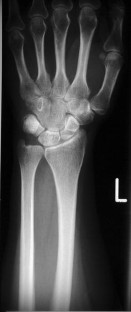

Fig. 1

The mean ulnar variance was 2.17 ± 1.56 mm preoperatively and after the ulnar shortening osteotomy −1.36 ± 1.67 mm (p < 0.05). Radiological consolidation of the osteotomy could be shown in 91 wrists 6 months postoperatively. Patients rated the preoperative pain level at a VAS 7.9 ± 1.7 which decreased to a of VAS 2.4 ± 2.5 (p < 0.05). 19 patients complained of mechanical irritation. There was no neurological irritation.